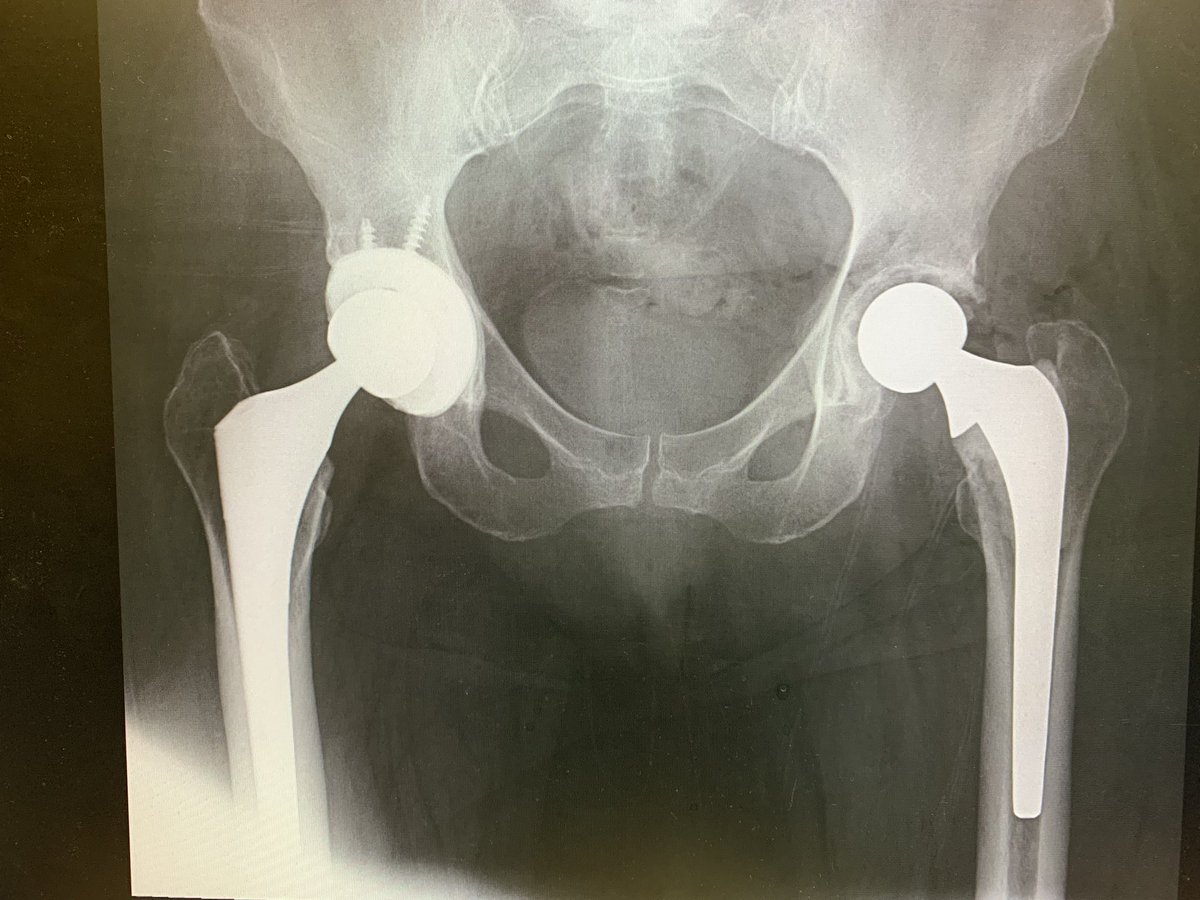

New Years brought me 2 distal femoral replacements 🤔. Not sure if that is a good sign or not, especially since I have had a lot of my revisions waiting because of COVID restrictions. 2022 may be a long year. #orthotwitter

@depurhro revised plus ORIF in my hands. In older patients I have also tended to extend fixation across the entire femur for prophylactic femur protection. Pics of recent case but press fit stem. Slightly different concepts. ?anyone else prophylactic long femur fixation?